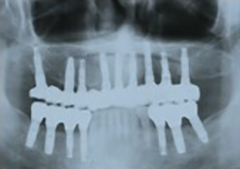

インプラントの埋入位置や角度を最適化し顎にかかる力を均等にすることで、上下顎それぞれ最少4本(合計8本)のインプラント埋入で全顎の人工歯を支えることが可能です。

そして、最少4本のインプラントで治療できるAll-on-4™も適応できないほど、上顎の骨が萎縮しているケースで行うのがザイゴマインプラントです。

ザイゴマインプラントは、一般的なものよりも長いインプラント体を顎(ザイゴマ)まで埋め込むことで、インプラント治療を可能にする方法。

通常、骨が足りない場合は骨造成を行って骨を増やすなどの処置が必要で治療に長期を要しますが、ザイゴマインプラントなら、あらゆる症例の患者さまに対し、手術当日に人工歯を固定することが可能です。